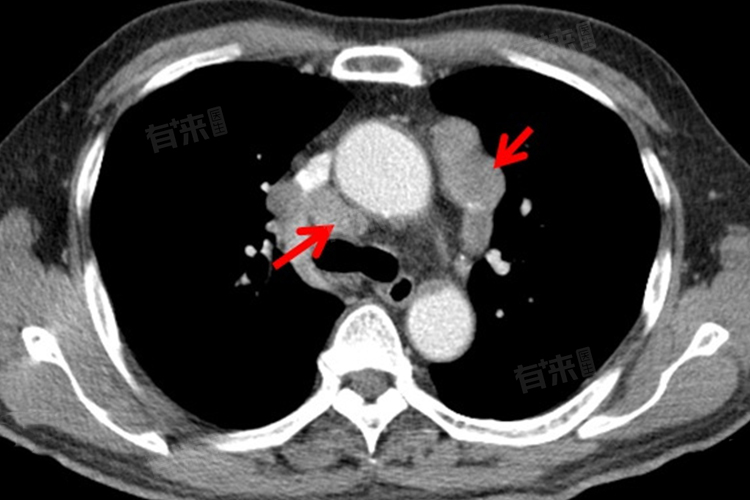

纵隔及右肺门淋巴结钙化是指淋巴结组织内出现钙盐沉积,导致淋巴结在影像学上呈现高密度影。这种钙化现象多数是由于淋巴结曾受到细菌的侵扰,导致炎症反应。在炎症过程中,坏死组织被机体吸收后钙盐沉积在淋巴结内,最终形成钙化,也可能是由于慢性炎症或其他疾病治愈后留下的痕迹。

- 通过胸部X线、CT扫描等影像学检查可以评估纵隔及右肺门淋巴结的钙化情况;必要时可进行活检以确定是否存在肿瘤或其他异常情况。